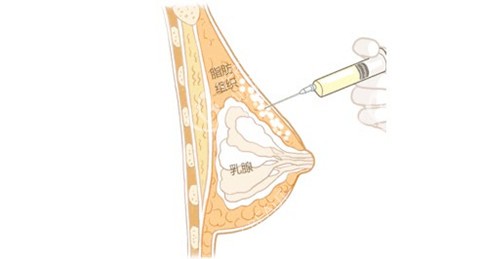

假体隆胸:技术优势藏在“细节里”

作为医院“招牌项目”,假体隆胸的技术优势主要有三点:一是“双平面剥离”,假体部分在胸大肌下、部分在乳腺后,既避免了“硬邦邦”的手感,又能支撑起自然乳沟;二是“小切口精细操作”,切口仅3-4cm,缝合用的是可吸收线,疗养时间短,我认识的姐妹术后7天就能正常上班;三是假体库超全,曼托、傲诺拉、宝俪等主流品牌都有,医生会根据身高、肩宽、胸距定制方案。